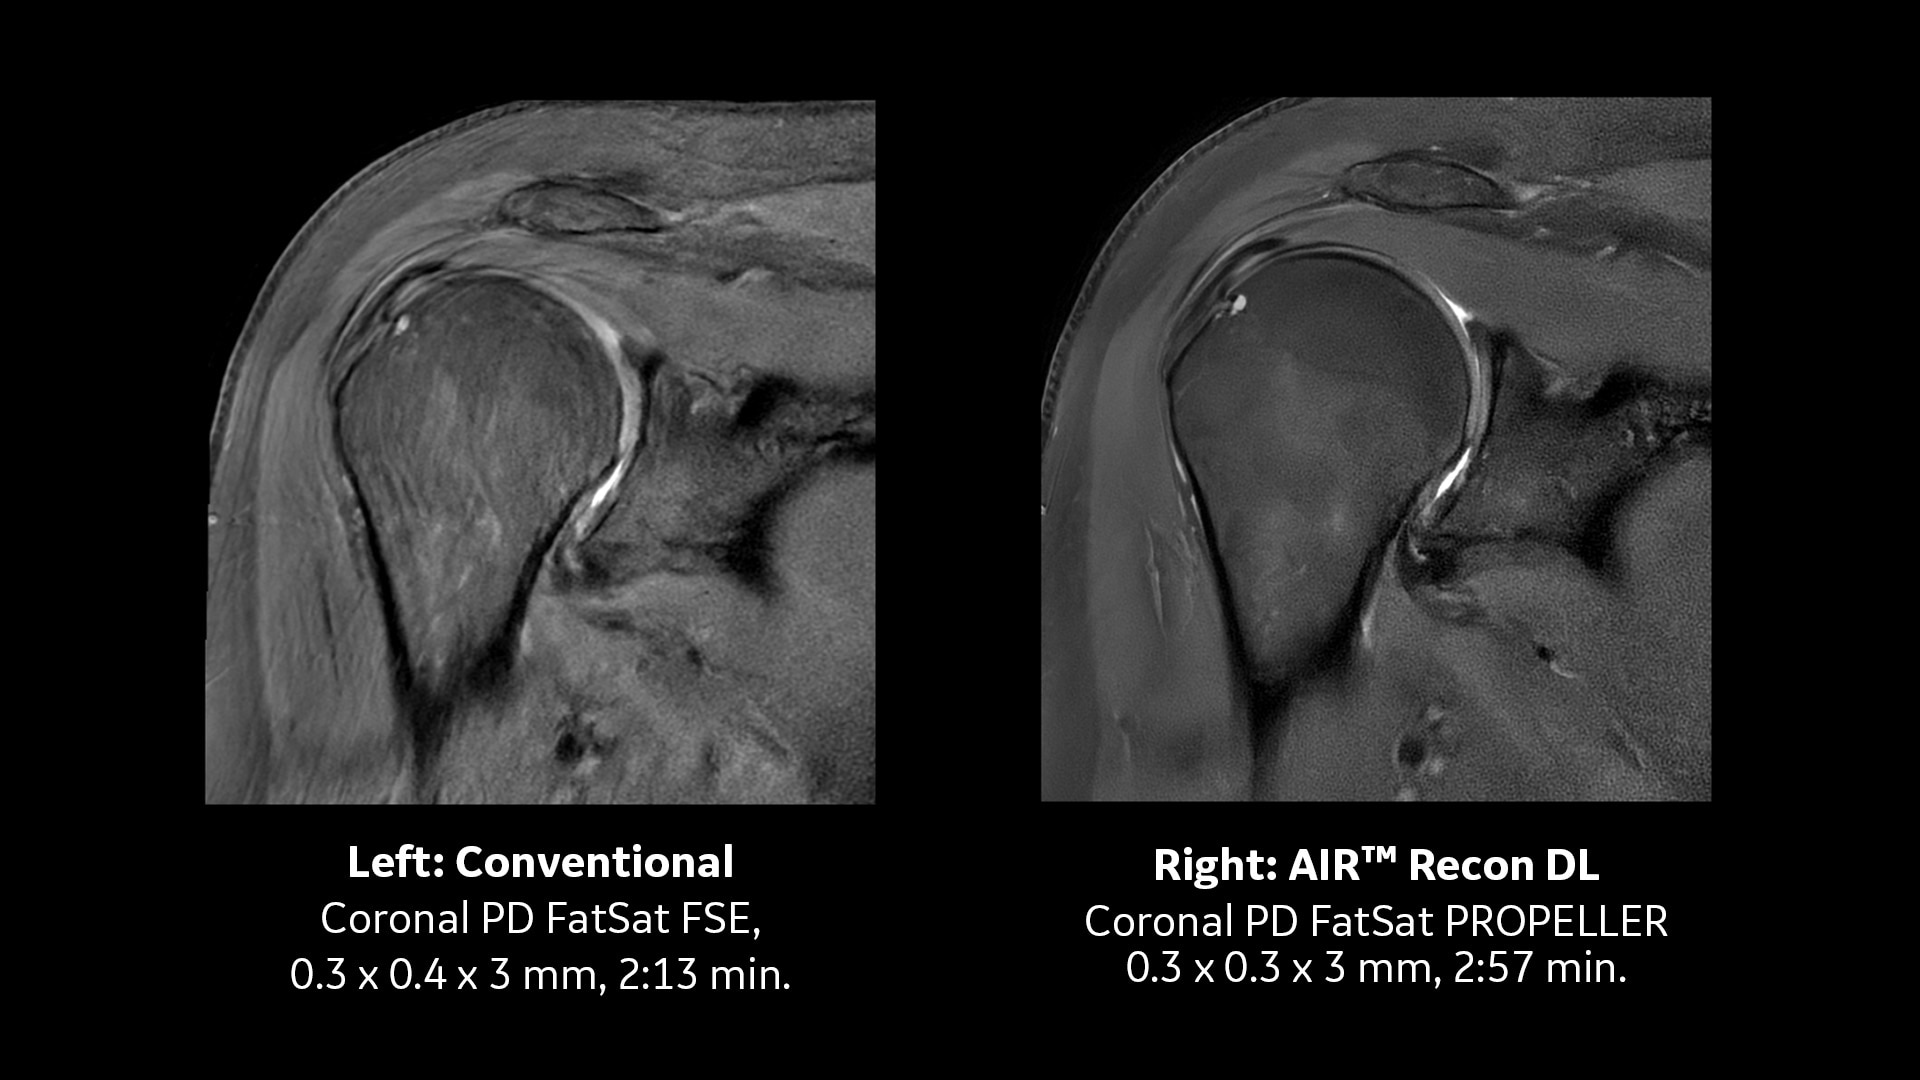

MR-Bildrekonstruktion mit AIR Recon DL

Maximieren Sie die Leistung Ihres MRT-Systems: Profitieren Sie von außergewöhnlicher Bildqualität – ganz ohne verlängerte Scanzeiten.

Schärfer sehen mit Deep Learning

AIR™ Recon DL erhöht das SNR und verbessert die Bildschärfe um bis zu 60 % – für beeindruckende Bildqualität bei jeder Untersuchung.

AIR Recon DL hat die Magnetresonanztomographie (MRT) durch seinen Deep-Learning-basierten Bildrekonstruktionsalgorithmus grundlegend verändert. Schätzungen zufolge wurden seit der Markteinführung im Jahr 2020 über 80 Millionen Patient:innen mit dieser Technologie untersucht.*Im Rahmen der Vision von GE HealthCare entwickelt sich AIR Recon DL kontinuierlich weiter und wird um eine breitere klinische Abdeckung erweitert. Kürzlich wurde AIR Recon DL um bewegungsrobuste PROPELLER-Sequenzen sowie um 3D-Bildgebungsfunktionen ergänzt.Sehen Sie sich die neueste Entwicklung selbst an.